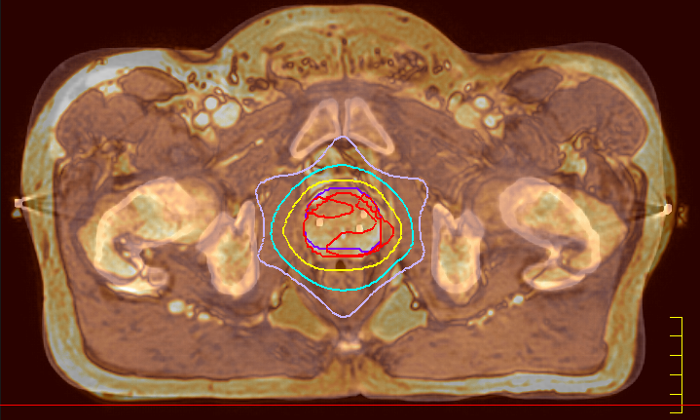

With its exceptional soft-tissue visualization capabilities and wide range of image contrasts, MRI has become a powerful tool to help more precisely define tumor boundaries. This is particularly important as it has been established that there is a high degree of uncertainty in target volume delineation, and it is even reported to represent the largest uncertainty in the entire radiotherapy process for most tumor sites**. Better visualization of the target area and nearby organs-at-risk is a key factor in enhancing target volume delineation. MRI’s expanding role also can be attributed to its functional imaging capabilities, which can inform both target characterization and treatment response.

The ability to tune contrasts can provide even more valuable information about tumor characteristics and tumor extent to facilitate enhanced delineation, and also provides possibilities for dose boosting strategies.

Innovative strategies in MRI-only simulation have made it possible to derive CT-like electron density information from MR imaging data. This capability enables physicians to use MRI as the radiotherapy department’s primary imaging modality for specific applications to eliminate tedious and error-prone CT-MR registration and simplify workflows.

Our innovative MRCAT (MR for Calculating ATtenuation) clinical applications lets you plan radiation therapy using MRI as primary imaging modality. Within just one, fast MR exam, MRCAT provides both excellent soft-tissue contrast for target and OAR delineation and CT-like density information for dose calculations.